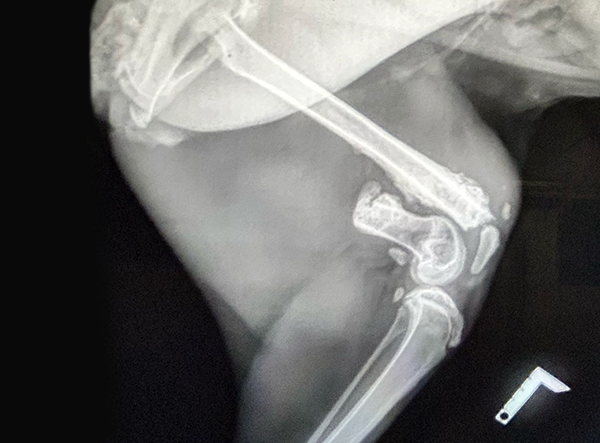

In April 2025, a stunning caracal suffering from a femur fracture began its road to recovery — and is now on its way to roaming freely in the wild.

The femur fracture was surgically treated by Dr. Matan Or, using a 3.5 LeiLOX Locking Bridge Plate to provide stable fixation and support the healing process. The LeiLOX system is designed to offer reliable stability while minimizing soft tissue disruption, which is crucial for optimal recovery and a safe return to natural mobility. Its locking mechanism ensures strong fixation, and the bridging technique helps maintain blood supply to the bone, supporting natural bone regeneration.

Since the operation, the caracal has been recovering well, with stable post-op results and steady healing progress. Although a full recovery will take time, the outlook is very encouraging, and the wild cat is expected to gradually regain strength and mobility.